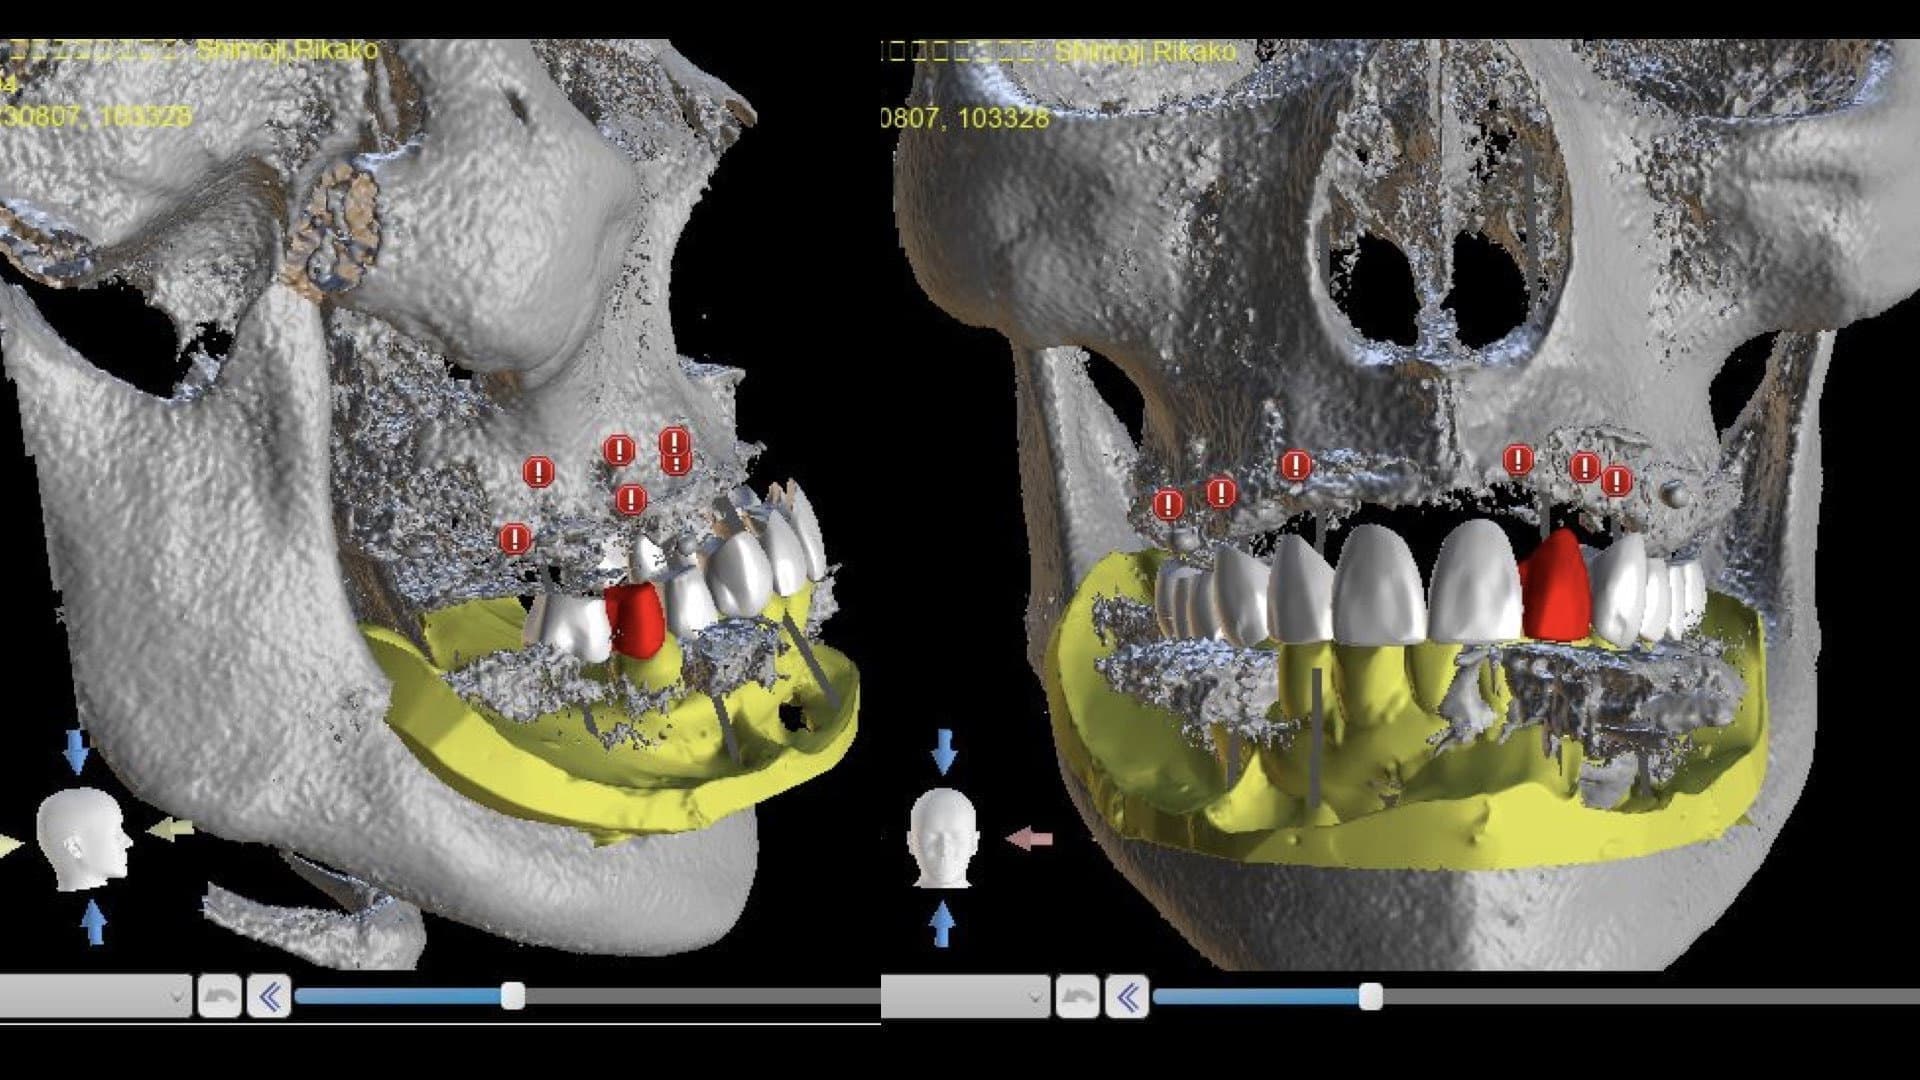

CT診断、CAD/CAMを活用した最先端の治療を行います

インプラント治療は失ってしまった歯の替わりに、 生体親和性が極めて高い純チタンで出来たインプラント(人工歯根)を歯肉内部にある顎の骨に埋め込み、その上に人工の歯を取り付け、噛み合わせを回復する治療法です。

CT設備完備

二次元のレントゲン(歯科医院にある通常のレントゲン)では見えなかったこと、分からなかったことが、歯科用CTなら正確な診査と診断ができ、安全性と治療のクオリティーを高めることが可能となります。

インプラント手術においてCT撮影は必須です。CT撮影を行うか否かも医院を選ぶうえでの判断材料にしていただければと思います。

ンピューター診断

手術時の「人為的なミス」を最小限に抑えることができる安全なインプラント治療を望まれる方。ぜひ、コンピューターインプラントを実施している医院での受診を強くお勧めします。